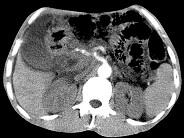

问题 女,50岁,中上腹疼痛,消瘦乏力,影像检查如下图,最佳的诊断是()

选项 A.慢性胰腺炎 B.急性胰腺炎 C.胰腺癌并腹膜后淋巴结转移 D.胰岛素瘤 E.腹膜后淋巴瘤

答案 C